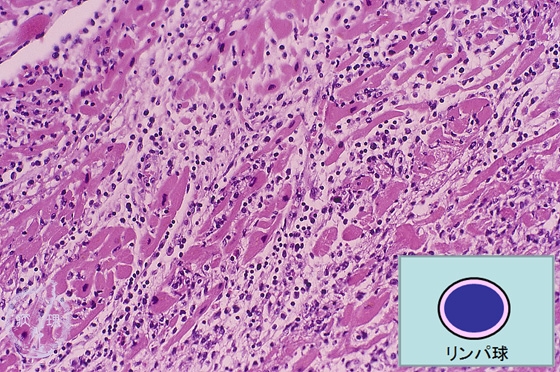

Microscopic image (HE, low power view): There is a marked inflammatory cell infiltrate consisting mainly of lymphocytes. Islands of entrapped myocardium show prominent necrotic change.